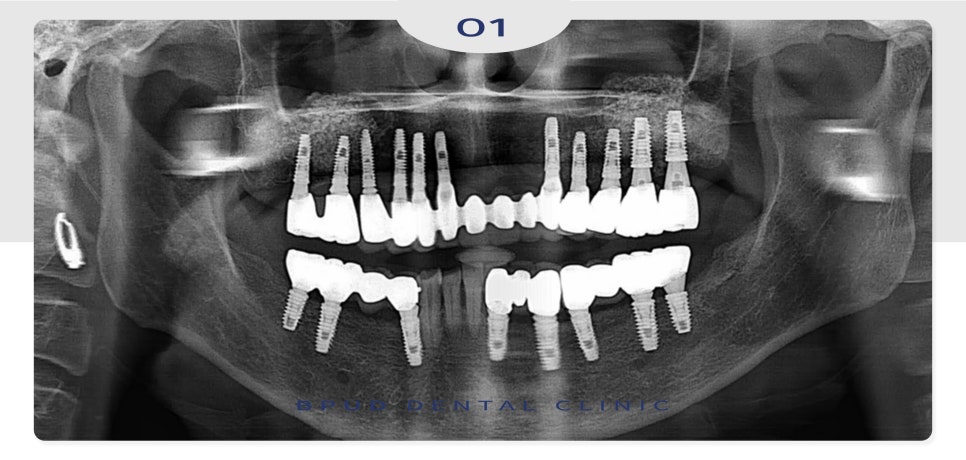

2024.07.09

환자분의 사정상,

오랫동안 미루고 미루다 잇몸이 불편해져

약 6년 뒤 내원하셨을 때는

이미 양쪽 아래 어금니 부위와 앞니에

심한 골 소실이 진행되어 신경관까지의 거리가

3mm 정도 남아 제거가 필요한 상태였는데요.